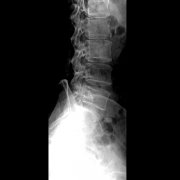

穿透能力增强 X 光机的管电压升高,会使 X 射线的能量增加。就像光线穿透玻璃一样,能量越高的 X 射线穿透人体组织的能力就越强。 例如,在拍摄骨骼结构比较复杂的部位(如脊柱、...更多 -